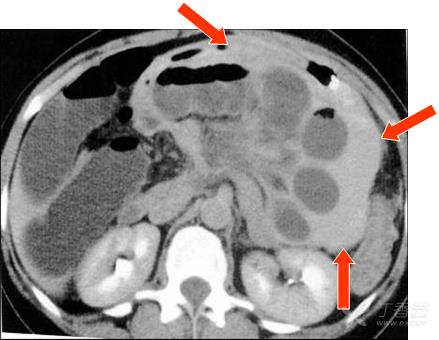

首次检查图像 1小时后复查,疝囊内肠管扩张明显,囊内积血(红箭),CT值高,示缺血严重。